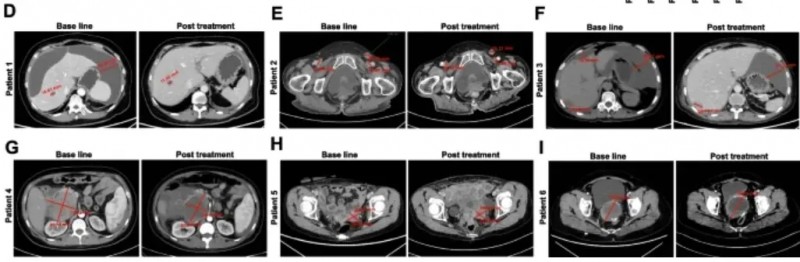

该研究共纳入10例转移性结直肠癌(CRC)患者,中位年龄58岁(范围48.8-67岁),其中80%(8/10)伴肝转移、50%(5/10)伴肺转移,所有患者入组后均接受CEA CAR-T细胞静脉输注。

结果显示:10例既往治疗进展(PD)的患者中,7例经CAR-T治疗后达病情稳定(SD),肿瘤直径仅轻微变化,其中P3、P5患者稳定期超30周(7.5个月)。

值得一提的是,其中两例典型病例的疗效尤为突出:

一例P9-2患者:在接受CEA CAR-T回输后,PET/CT显示肿瘤活动减弱、代谢活性显著降低。下图展示了CAR-T输注前(左图)、治疗4周后(右图)的PET/CT对比。

▲图源“Molecular Therapy”,版权归原作者所有,如无意中侵犯了知识产权,请联系我们删除

另一例P10患者:在接受DL4剂量CEA CAR-T治疗后,MRI证实肝内一处病灶缩小。下图展示了CAR-T治疗前(左图)、治疗4周后(右图)的MRI对比。